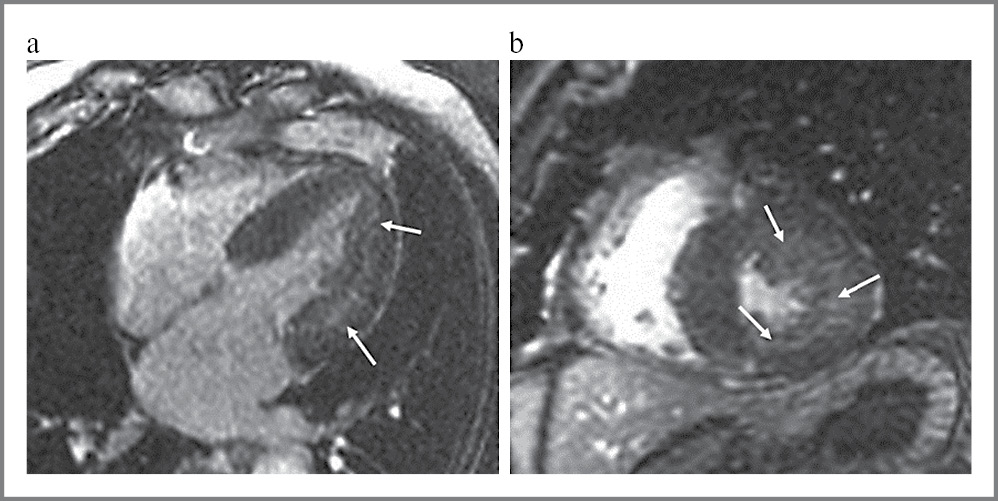

МРТ сердца с использованием внутривенного контрастирования гадолинием выполнялась с целью выявления диффузного миокардиального фиброза (МФ), который выявлен у большинства пациентов – у 53 (75,7%) человек, среди которых 21 женщина и 32 мужчины (рис. 1). Статистических различий между пациентами с наличием и отсутствием диффузного фиброза при МРТ по возрасту, полу, антропометрическим данным, уровню тиреоидных гормонов, СТГ, ИФР-1, частоте ремиссии, наличию НРПС, принимаемой терапии не выявлено. Обнаружено различие на уровне статистической тенденции между данными группами в зависимости от длительности заболевания: 5,5 [3; 10] и 10 [6, 5; 16, 5]; p=0,006 (табл. 1).

Рис. 1. Диффузное отсроченное накопление гадолиния по данным МРТ сердца: a – 4-камерная позиция; b – короткая ось.

Fig. 1. Diffuse delayed gadolinium uptake according to MRI of the heart: a – 4-chamber view; b – short axis.